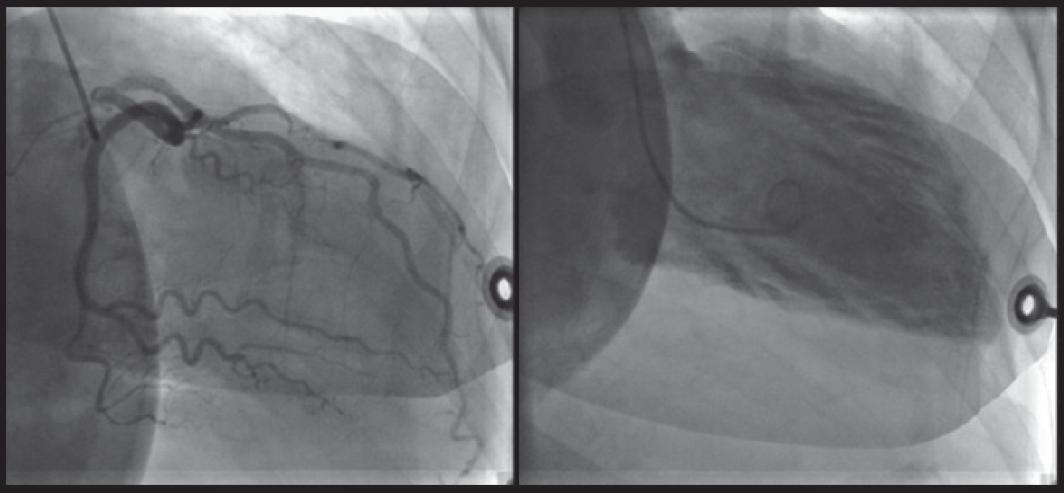

图2 一名患有Takotsubo心肌病女性的心室造影